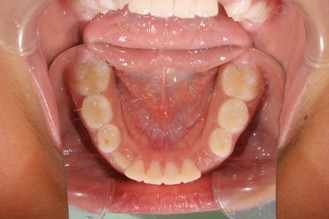

04:深い噛み合わせとガタガタの歯並び

矯正治療の症例写真

矯正治療終了後の症例写真

保定期間の写真

症例・治療内容について

• 主訴:上の歯と下の歯が逆に噛んでいるところがある

• 診断あるいは主な症状:交叉咬合

• 年齢:29歳(治療開始年齢)

• 治療に用いた主な装置:マルチブラケットによる歯列矯正

• 抜歯部位:なし

• 治療期間:2年1ヶ月

• 通院回数:25回(矯正治療を目的とした来院)

• 治療費概算:550,000円(税込)